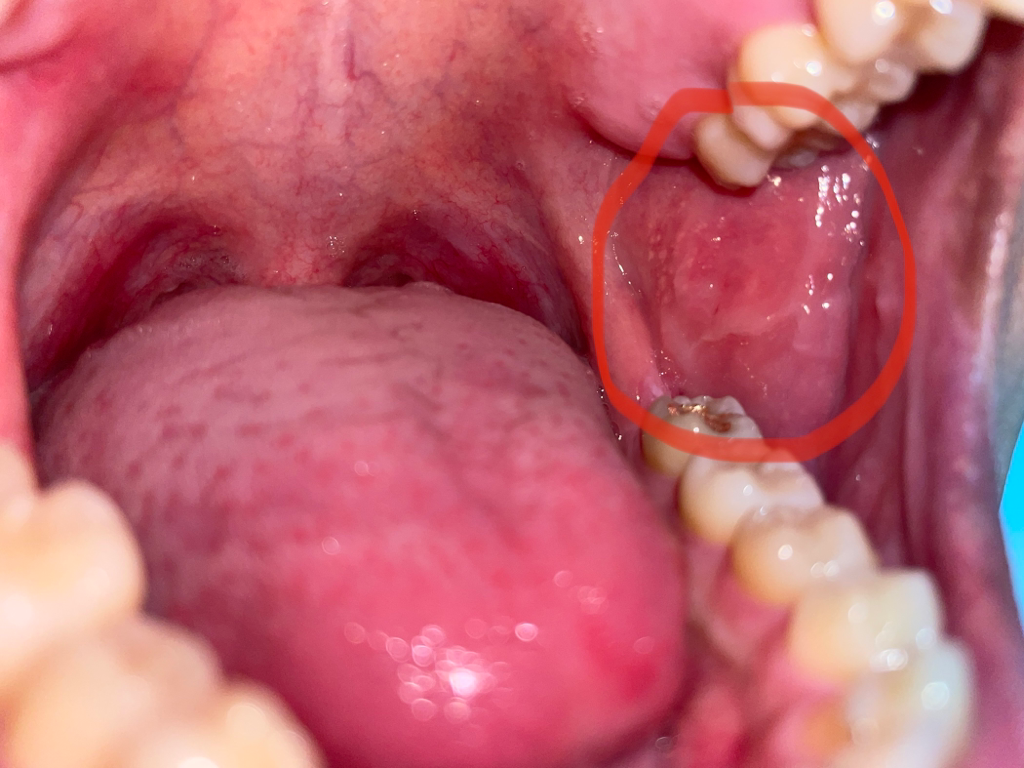

입속에 뭐가 났습니다. 뭔가 하얀 동그라미가 목구멍 근처에 잔뜩 생겼습니다. 이게 뭘까요?

제목 그대로 입니다 목구멍하고 가까운 입속 벽? 쪽에 하얀 동그라미 모양 물집같은 게 잔뜩 생겼습니다. 큰 병인가요? ㅠㅠ 보통 입병이랑 다르게 생긴 것 같아서요. 양쪽에 다 났어요.

일반적인 구내염의 증상으로 보이며 구내염의 양상은 조금씩 다르며 세균이나

진균에 의한 구내염에 따라 모양이 다를 수 있습니다. 심각한 질병 보다는 구내염

으로 인한 구강 내 변화로 보이며 시간이 지나면서 회복하는 경우가 대부분으로

치료가 반드시 필요하지는 않으나 비타민 복용과 충분한 수면이 재방을 줄일 수

있습니다.